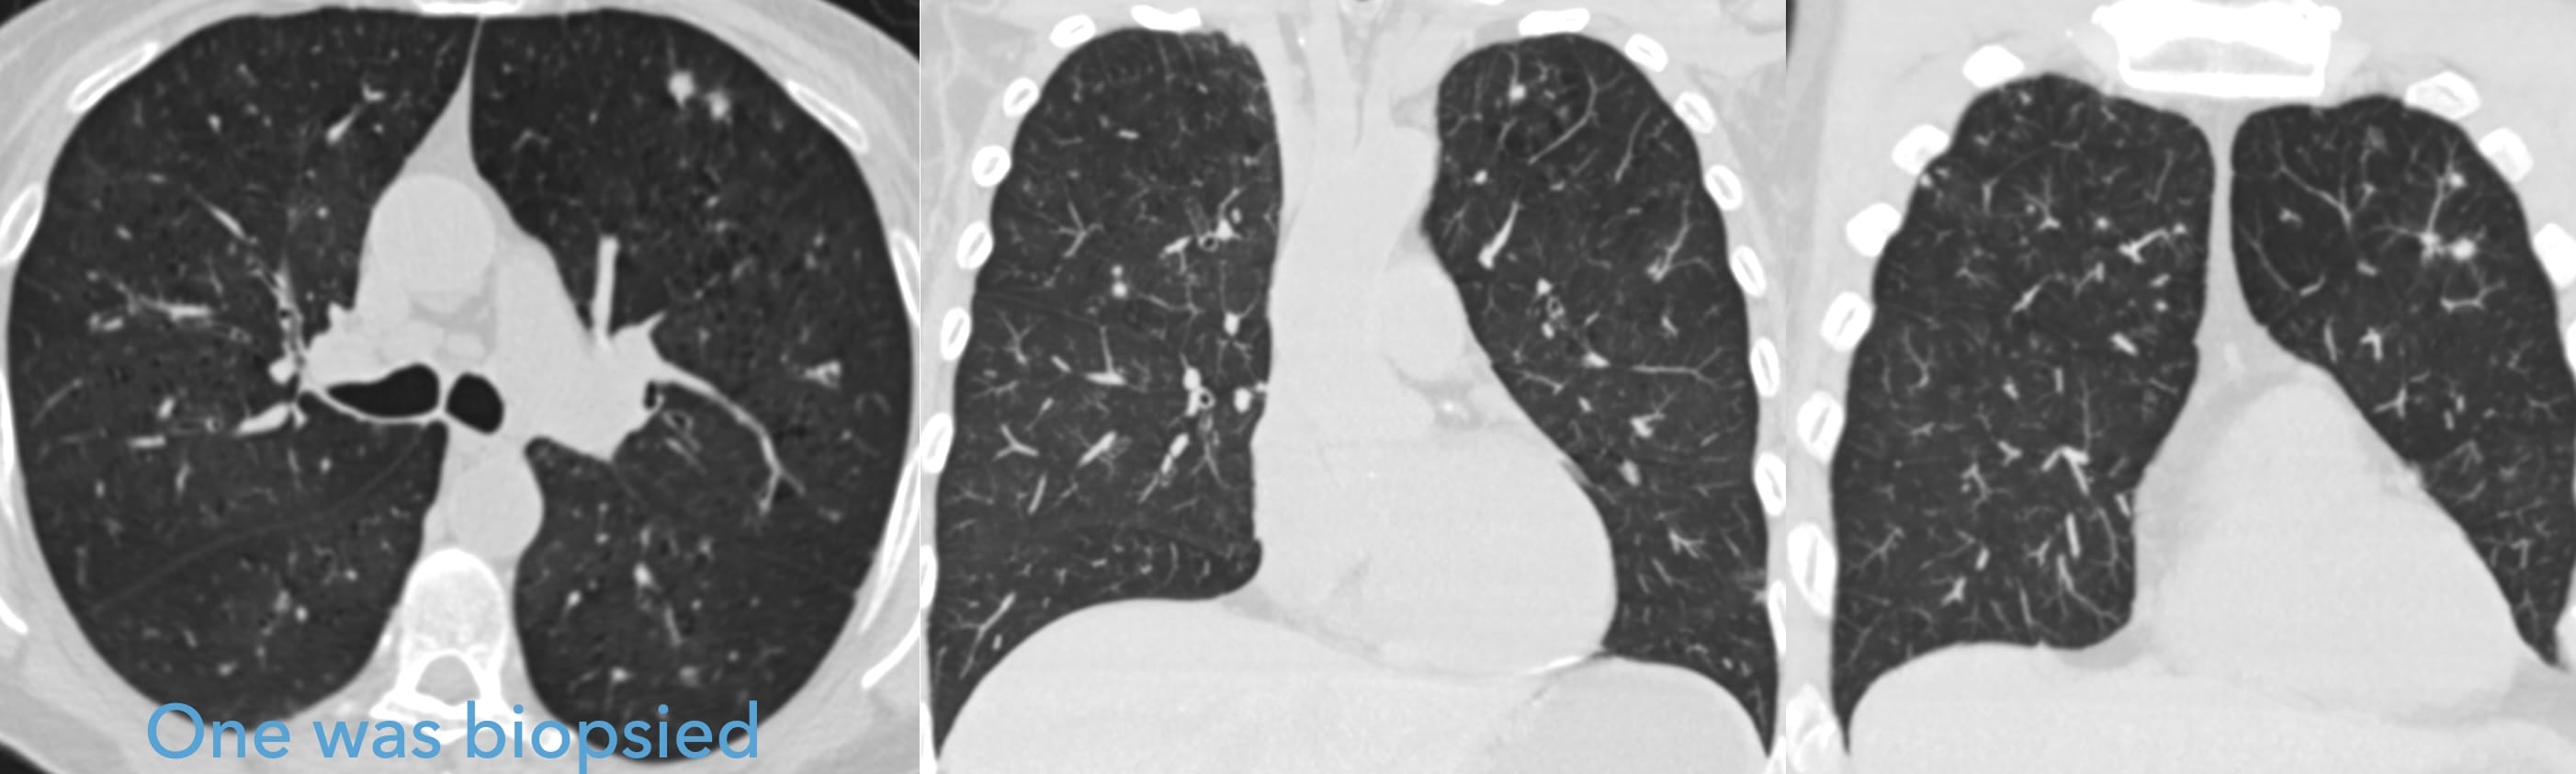

Should we really discard DIP ?

Update of the International Multidisciplinary Classification of the Interstitial Pneumonias: An ERS/ATS Statement. Eur Respir J 2025; (https://doi.org/10.1183/13993003.00158-2025).

• Alveolar [Smoker’s] Macrophage Pneumonia (AMP) replaces Desquamative Interstitial Pneumonia

Finally! Why did it take so long ?

Pathology

Distinctive accumulation of swaths of “ropey collagen,” particularly in the subpleural lungs

arrow: ropey collagen arrowhead: pigmented smoker’s macrophages

Source: Vehar, et al.SRIF https://doi.org/10.1093/ajcp/aqac144

Yes, we cannot tell how much of the opacity is SRIF versus Smoker’s Macrophages versus both!

Suggested reporting terminology

“Findings of Smoker’s Lung are present in the form of: centrilobular emphysema in the upper lungs and patchy pulmonary ground glass opacities, consistent with accumulation of Smoker’s Macrophages and, possibly, Smoking-Related Interstitial Fibrosis.”